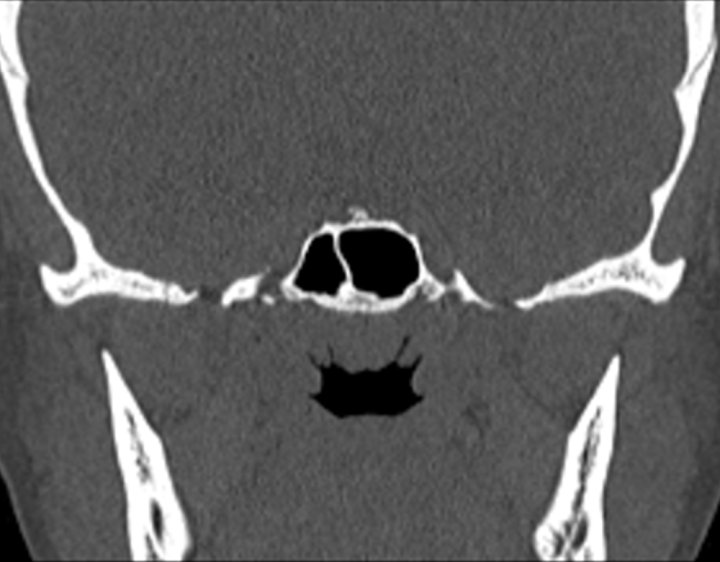

Click any image for labels.